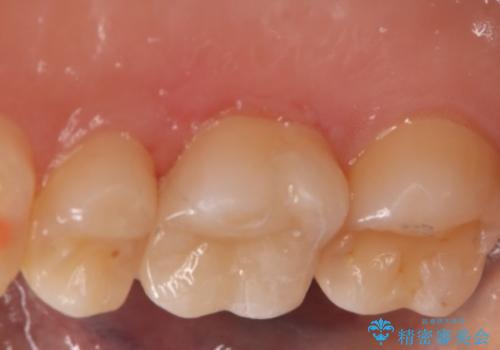

- 右上6番の虫歯治療を主訴に来院された患者様です。

切削量・形態を考慮し、セラミックインレーでの治療を計画しました。

保険の材料が劣化し中で虫歯が進行していたので、全て取り除いた上で形を整え型をとりインレーをセットしています。